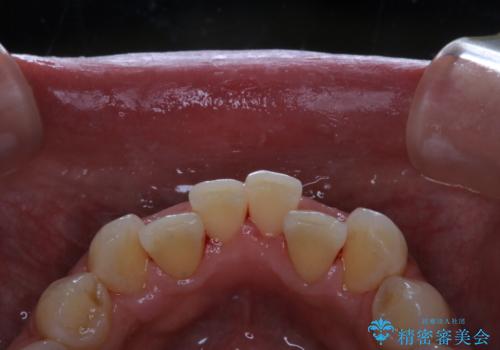

- 歯科でのクリーニングが5・6年ぶりで、全体をきれいにしたいとのことで来院されました。PMTC60分コースを行いました。

PMTCとは「Professional Mechanical Tooth Cleaning」の略で、専用の機器を使った歯のクリーニングです。

PMTCは誰もが実施できるというわけではなく、歯科医師や歯科衛生士によるプロフェッショナルケアです。

審美的面だけではなく、歯周病や虫歯・口臭などのリスクを予防することができます。

汚れを除去することにより、症状の早期発見につながります。

定期的に歯科医院に来院し、PMTCを行うことが大切です。

クリーニング希望の際には担当の歯科衛生士が、患者様1人1人の歯周病リスク・ブラッシングスキルなども確認します。

単なる磨き方の指導だけではなく、歯並びや歯肉の状態、ライフスタイルなどにより、患者様に適した歯ブラシや歯磨剤の選択をしたり、お口のお悩みについてのご相談も承っております。

定期的にメンテナンスを行うことで、なにかあった時の早期発見につながります。